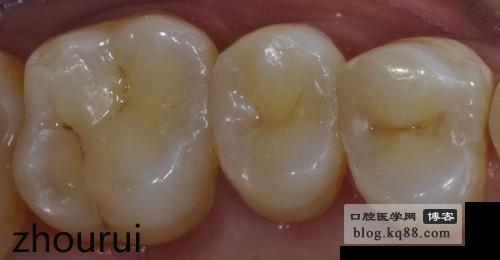

術(shù)前

橡皮障配合beyond鄰面成系統(tǒng)初步完成(外展隙有粘接劑飛邊)

刀片修整后初步調(diào)牙合(盡量避免金剛砂器械)

隔日三步拋光法拋光(牙齦乳頭恢復(fù))

一周復(fù)查窩溝染色線偏寬

精細(xì)拋光后